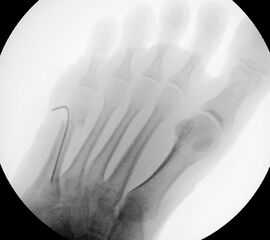

In der Regel bestehen aktive Wachstumsfugen bei Mädchen bis zum 12. und bei Jungen bis zum 14. Lebensjahr, mit Abweichungen von einem Jahr nach unten und nach oben. Präzise Informationen unter anderem darüber gibt das präoperative Röntgenbild (Abb. 2).

Abb. 2 a-c: offene Wachstumsfugen MT I Basis und Zehen (a), teilweise geöffnete Wachstumsfugen (b) und geschlossene Wachstumsfugen (c).